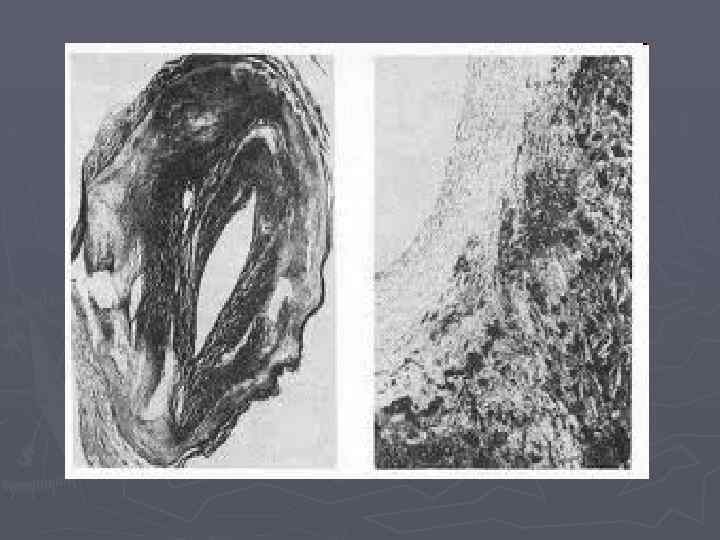

Бауырдың некроздануы

Бауырдағы ошақты некроз